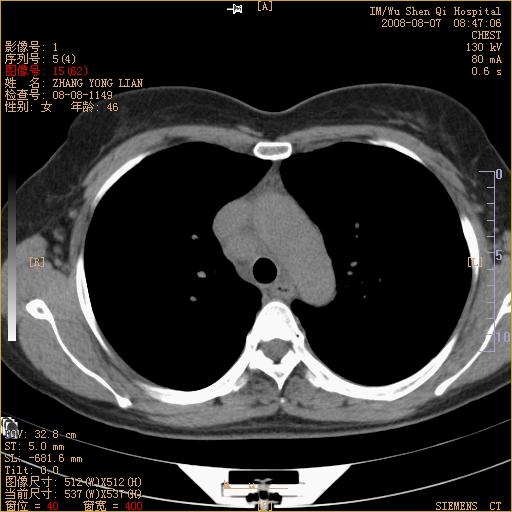

标题: CT15050:女,46岁,咳嗽胸痛一月余 [打印本页]

标题: CT15050:女,46岁,咳嗽胸痛一月余

纵隔窗没发全,左下肺近胸膜处结节。有长毛刺,纵隔淋巴结增大,不排除恶性病变。

考虑左肺下叶后基底段周围型肺癌伴纵隔淋巴结转移可能性大。

左下肺ca并纵隔及左肺门区淋巴结转移。

脾脏低密度结节转移不排除。

1)考虑左肺下叶后基底段周围型肺癌伴纵隔淋巴结转移。2)脾内低密度灶,性质待定;不排除转移瘤可能。